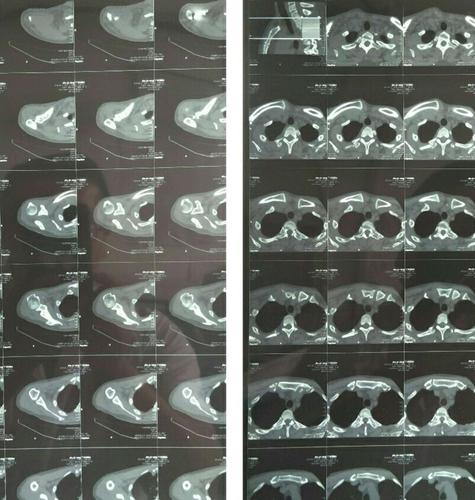

该患者行ct检查提示肩关节后脱位合并反bankart损伤 反hill-sachs

(肩锁关节 胸锁关节)ct平扫